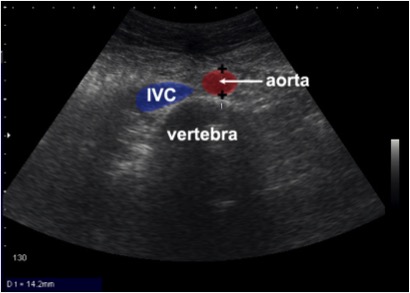

- Identify normal chest and abdominal anatomy

The RUQ should be divided into 3 zones.

1. Above/Below the diaphragm,

2. Morrison’s pouch (hepato-renal recess)

3. Para-colic gutter: Around the inferior hepatic edge/inferior pole of kidney

The key is to know your landmarks, and STOP, STAY and widely FAN through each zone well, adjusting your depth as necessary to keep the area of interest centered on your screen.

Start high to stay and fan (anterior to posterior) around the diaphragm. Then, SLIDE down into another rib space, stop, stay and fan around the entire kidney. An additional rib space may be necessary to evaluate the para-colic gutter.